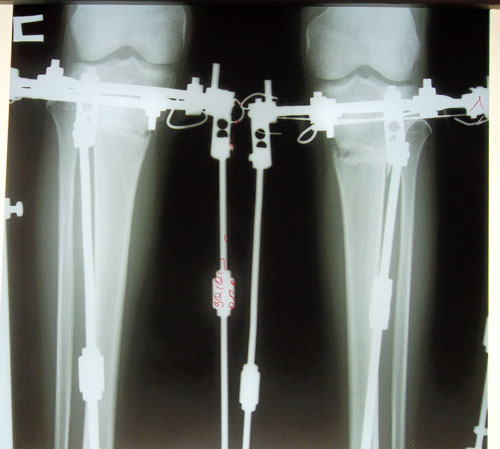

Ножки на сегодня

Ножки в норме, продолжаем фиксацию! Не забывайте про рентгеновский снимок в 2 месяца с момента операции. (с доставкой до адреса клиники). Девочки, это касается ВСЕХ!!!

Дата операции 02.07.2013г.

Дата снятия аппаратов 30.10.2013г.

Срок лечения 118 дней.